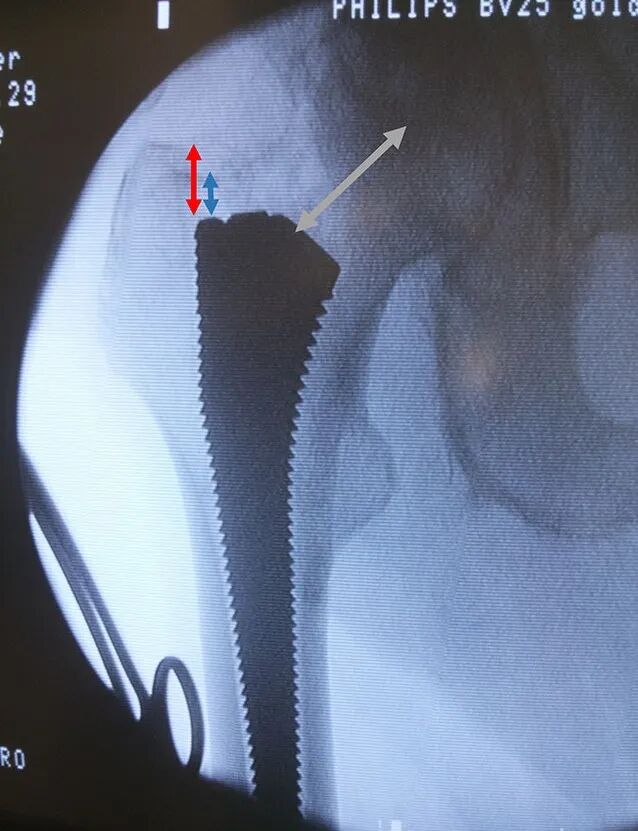

圆形股骨矩锉(貌似洛阳铲)开槽后,用股骨矩刮匙插入股骨髓腔,刮除股骨近端髓腔内侧的松质骨,以确保假体在髓腔内获得良好的皮质骨接触,然后用型号递进的绞刀或髓腔锉依此扩髓,髓腔锉填充满意且转子尖与髓腔锉肩部之间的距离约1.5cm为最佳,将髓腔锉留在髓腔内。

将试头和试颈插入内衬并定位到髋臼中,助手移动膝盖或脚,而主刀则移动腿部引导试颈与试头在髋臼内“对接”。检查腿长、稳定性(前、后、侧)、活动范围及撞击情况。如果存在屈曲挛缩,需松解股骨前部和/或髋臼前部的关节囊。进行X光检查以确认假体安装情况。